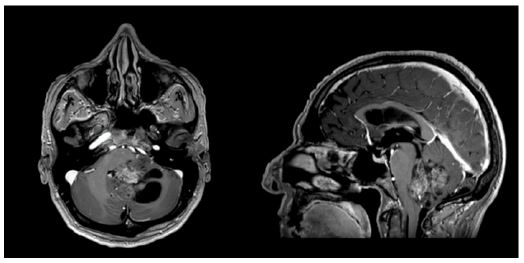

Patient - M, 66 yr. The patient presented with disequilibrium, unstable walking and multiple fallings without loss of consciousness during the previous months. Due to the persistence of symptoms, a brain Magnetic Resonance (MRI) was performed, showinga fourth ventricular lesion extending to the vermis and the left cerebellar hemisphere, characterized by un even contrast enhancement associated with initial signs of hydrocephalus (Figure 1).

A brain MRI with and without gadolinium was performed 45 days after surgery, showing complete excision of the lesion (gross total resection) and resolution of the preoperative hydrocephalus (Figure 2).